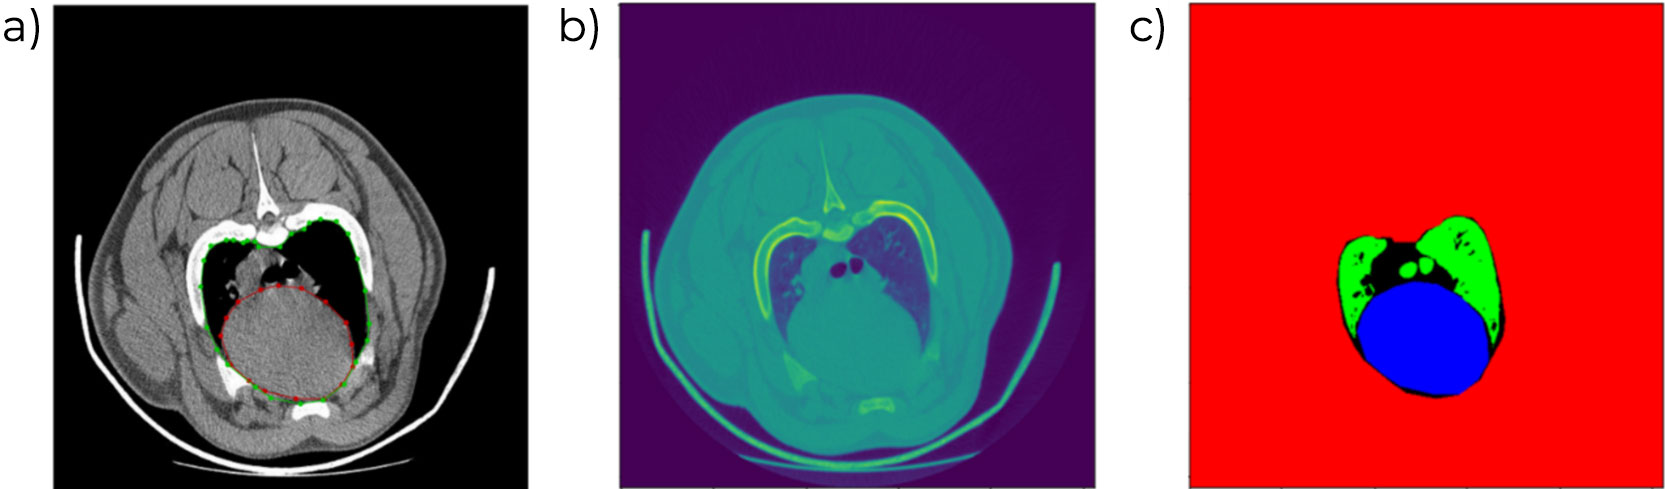

O processo de análise de imagens foi realizado manualmente durante anos, identificando as diferentes áreas anatómicas e os tipos de tecido (osso, gordura e músculo), o que já representava um avanço significativo. Em 2016, foi implementado um método mais automatizado de análise de imagens por TC, permitindo a diferenciação dos diferentes cortes principais (presunto, pá, lombo e barriga). O aparecimento das tecnologias de Inteligência Artificial (IA) foi fundamental para a automatização deste processo, essencial para o escalonamento desta ferramenta e o aumento da eficiência do número de animais analisados.

No obstante, la IA requiere de un proceso de entrenamiento previo para lo cual es necesaria una base de datos enorme con imágenes previamente analizadas que sirvan de modelo. En nuestro caso, esa base de datos estaba disponible gracias a los años previos de análisis con TC, durante los cuales ya se había avanzado notablemente en la segmentación de los tejidos e identificación en la imagen de los voxel (unidades más pequeñas que componen una imagen tridimensional, similar a los pixel en una fotografía) que pertenecen a tejidos diferentes.